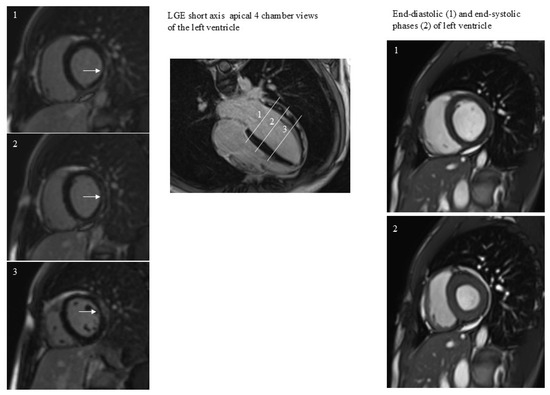

All patients performed CMR examination without any kind of complication. The time interval between COVID-19 diagnosis and CMR was 409 ± 26 days. The prevalence of positive LGE was 33% (17/51). LGE was present in the lateral wall in all patients except for one patient, with LGE positivity at the level of the interventricular septum (Figure 1). In this patient LGE was associated with abnormal regional wall motion (hypokinesia). In general, patients, both with and without positive LGE, had similar CMR variable values (Table 1). The factor associated with LGE was the duration of hospitalization (Figure 2).

Figure 1.

A case of subepicardial and intramyocardial LGE (arrows). LGE persistence was not associated with dilatation or regional dysfunction of the left ventricle. The 3 white lines correspond to the 3 short axes planes on the left.